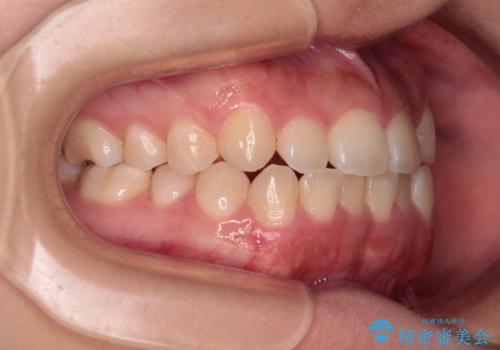

前歯のクロスバイトを改善 インビザライン・モデレートによる矯正治療

- 上下前歯のクロスバイトと叢生を気にして来院された患者様です。

インビザラインでの治療を希望されていて、デコボコの程度が中等度であり、安価なパッケージにて対応可能と判断されたため、インビザライン・モデレートを用いて矯正治療を行うこととしました。